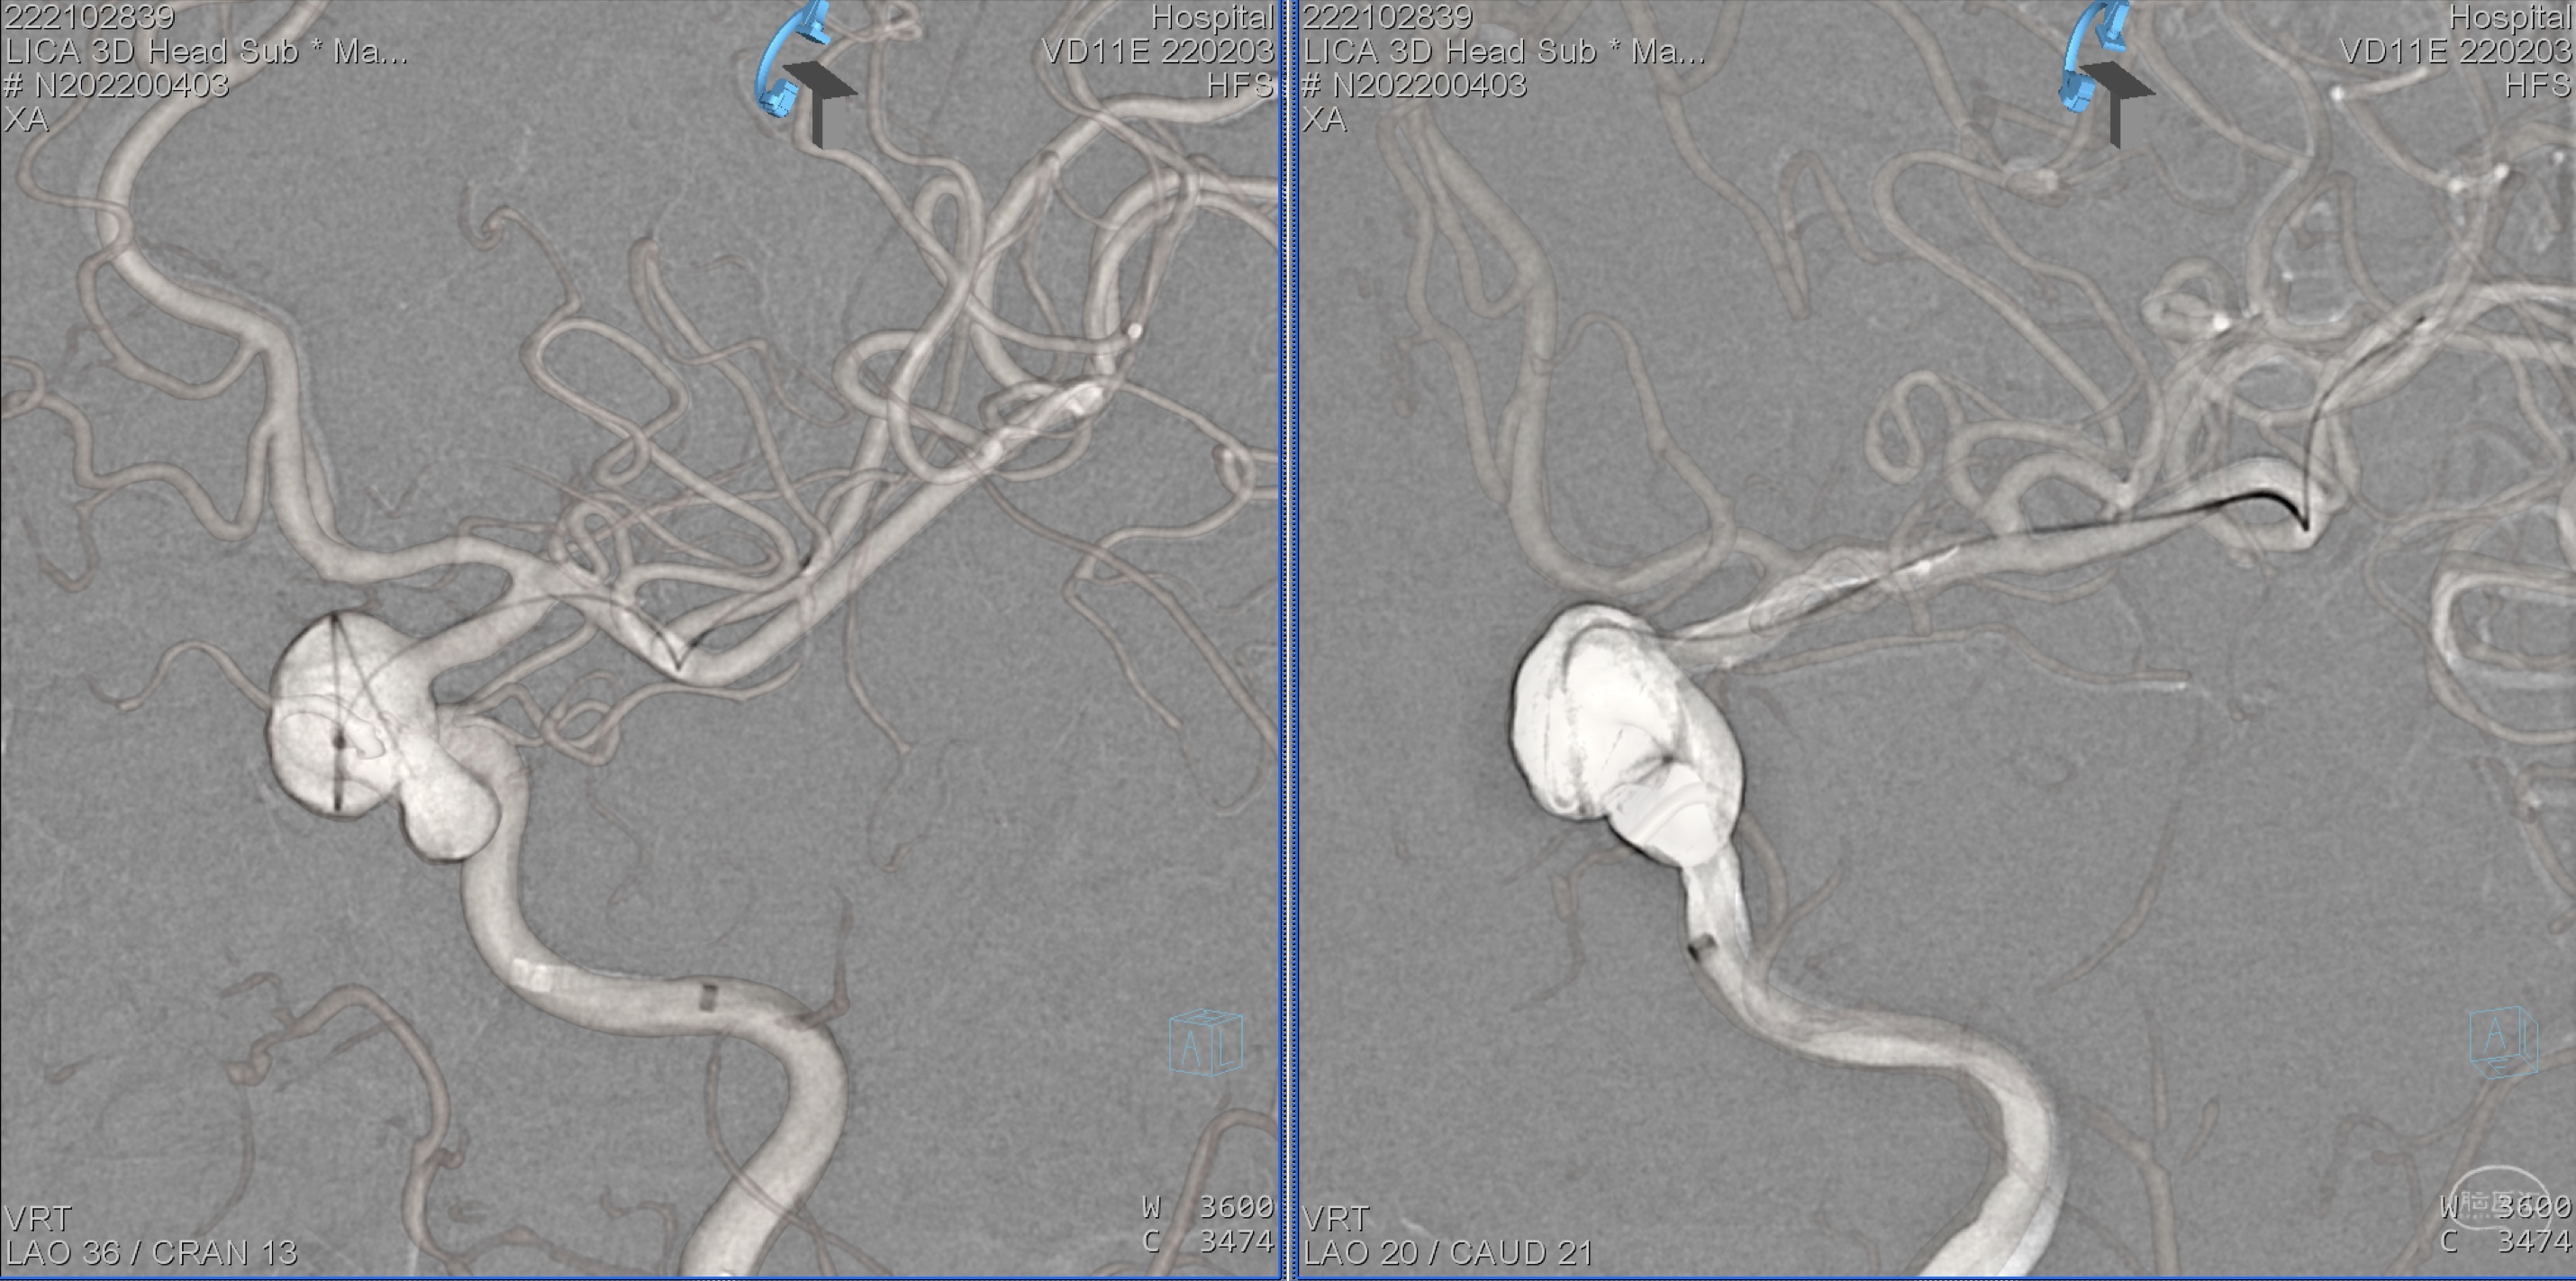

左侧颈内动脉三维重建:眼动脉段动脉瘤。

左侧颈内动脉三维重建:眼动脉段动脉瘤,海绵窦段血管略扩张。

详细测量载瘤动脉远近段动脉直径。

详细测量载瘤动脉远近段动脉直径。